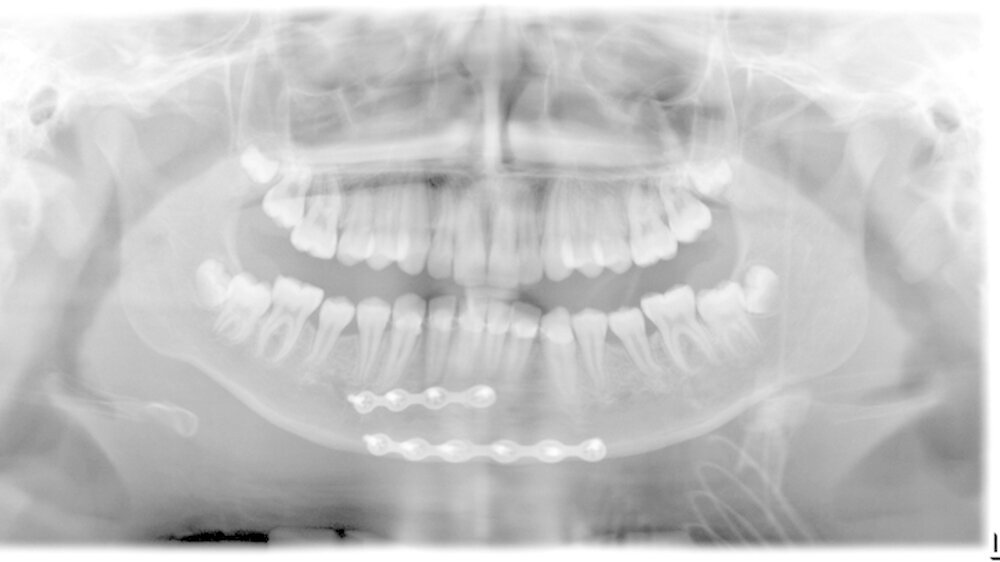

Ein 11-jähriges Mädchen erlitt verursacht durch den Familienhund multiple Bisswunden im gesamten Gesichtsbereich: Es zeigten sich scheinbar geringer relevante Einbissstellen submandibulär. Bei eingehender klinischer Untersuchung wurden jedoch eine Diastase zwischen 42 und 43, abnorme Beweglichkeit, Okklusionsstörungen sowie traumabedingt drittgradig gelockerte Zähne 32 bis 42 auffällig.

Nach durchgeführter Röntgendiagnostik (konventionelle Panoramaschichtaufnahme) bestätigte sich eine rechtsparamediane und nach links verlaufenden Schrägfraktur. Es erfolgte die plastische Sofortrekonstruktion - an Stirn, linksperiorbital und lateralem Lidwinkel links, linker Wange, rechtstemporal sowie Kinnpartie beidseits - sowie die osteosynthetische Versorgung der paramedianen Unterkieferfraktur mittels Miniplatten in Intubationsnarkose. Tetanusschutz der Patientin bestand, das Tier war gegen Tollwut geimpft.